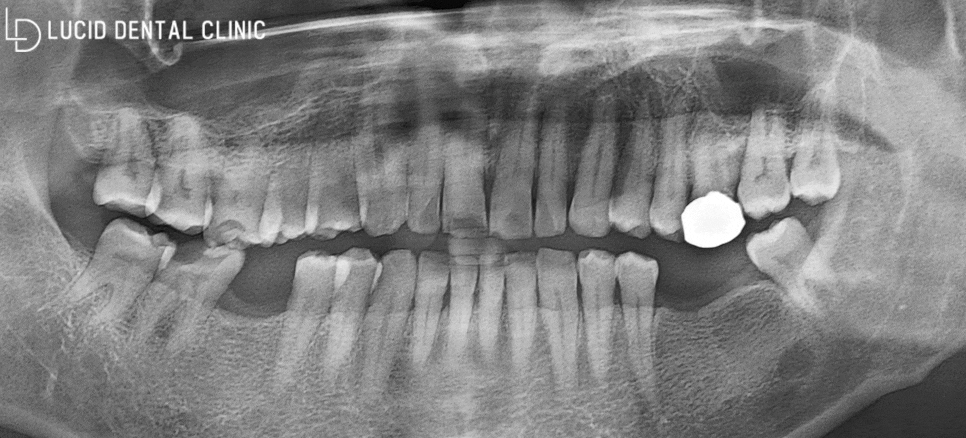

초진 파노라마 엑스레이로 확인한 결과,

화살표로 표시해 드린 것처럼

어금니 치아 두 개를 발치하셨네요

그런데 생각보다 꽤 많은 양의

문제점이 나타나고 있었습니다.

동그라미로 표시해 드린 곳을 보면,

거뭇한 부분이 크게 나타나고 있죠?

현재 충치 감염이 크게 일어나면서

(1) 치관(머리 부분)이 사라지고 있었고,

(2) 조금씩 정출되며 교합에

방해를 주고 있었습니다.

더 방치하다간 자연 발치로 이어질 가능성이 크고,

다른 곳에도 영향을 끼칠 수 있다고 판단했습니다.